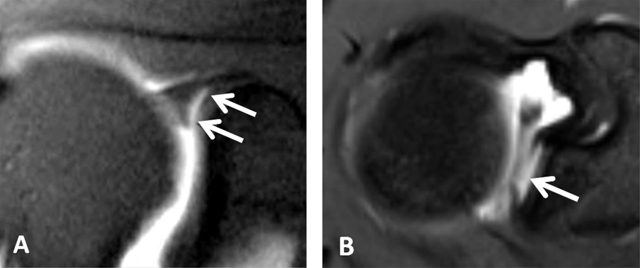

Figure 4

Normal humeral head versus Hill-Sachs lesion. (A) On the axial T2 gradient echo weighted MR image, there is a slight flattening of the posteroinferior surface of the humeral head (arrow), which is a normal finding. (B) Axial fat saturated T2-weighted MR image obtained at the level of the coracoid process (arrowhead, B) typically shows a Hill-Sachs defect (arrow) in a patient with history of anterior shoulder dislocation.